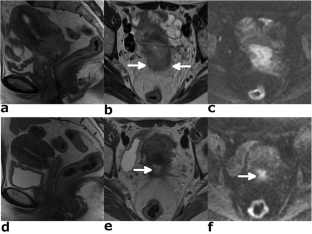

Fig. 1

Fig. 2

Fig. 3

Fig. 4

Fig. 5

Fig. 6